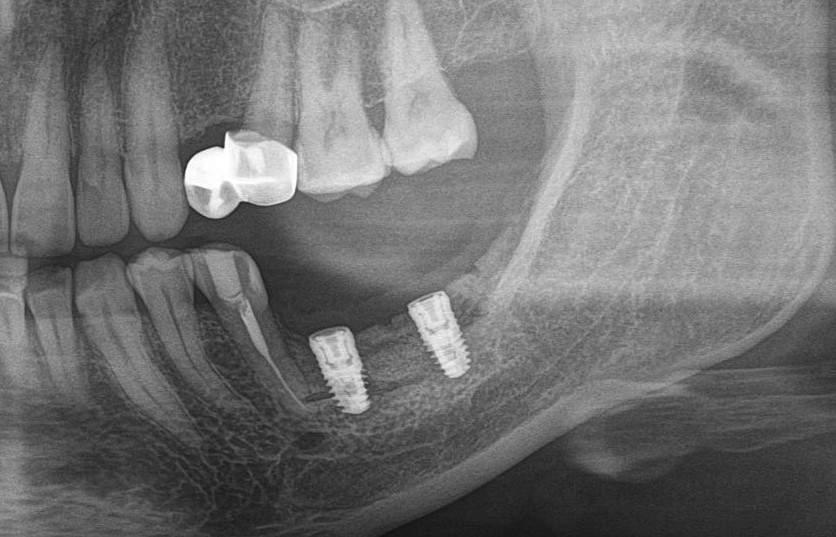

После операции мы делаем контрольные снимки. Это может быть ортопантомография:

или конусно-лучевая компьютерная томография. Как вам больше нравится.

Результат остеопластики методом остетотомии мы можем оценить уже через 4 месяца. Перед этим сделаем контрольные снимки (слева «до», справа «через 4 мес»):